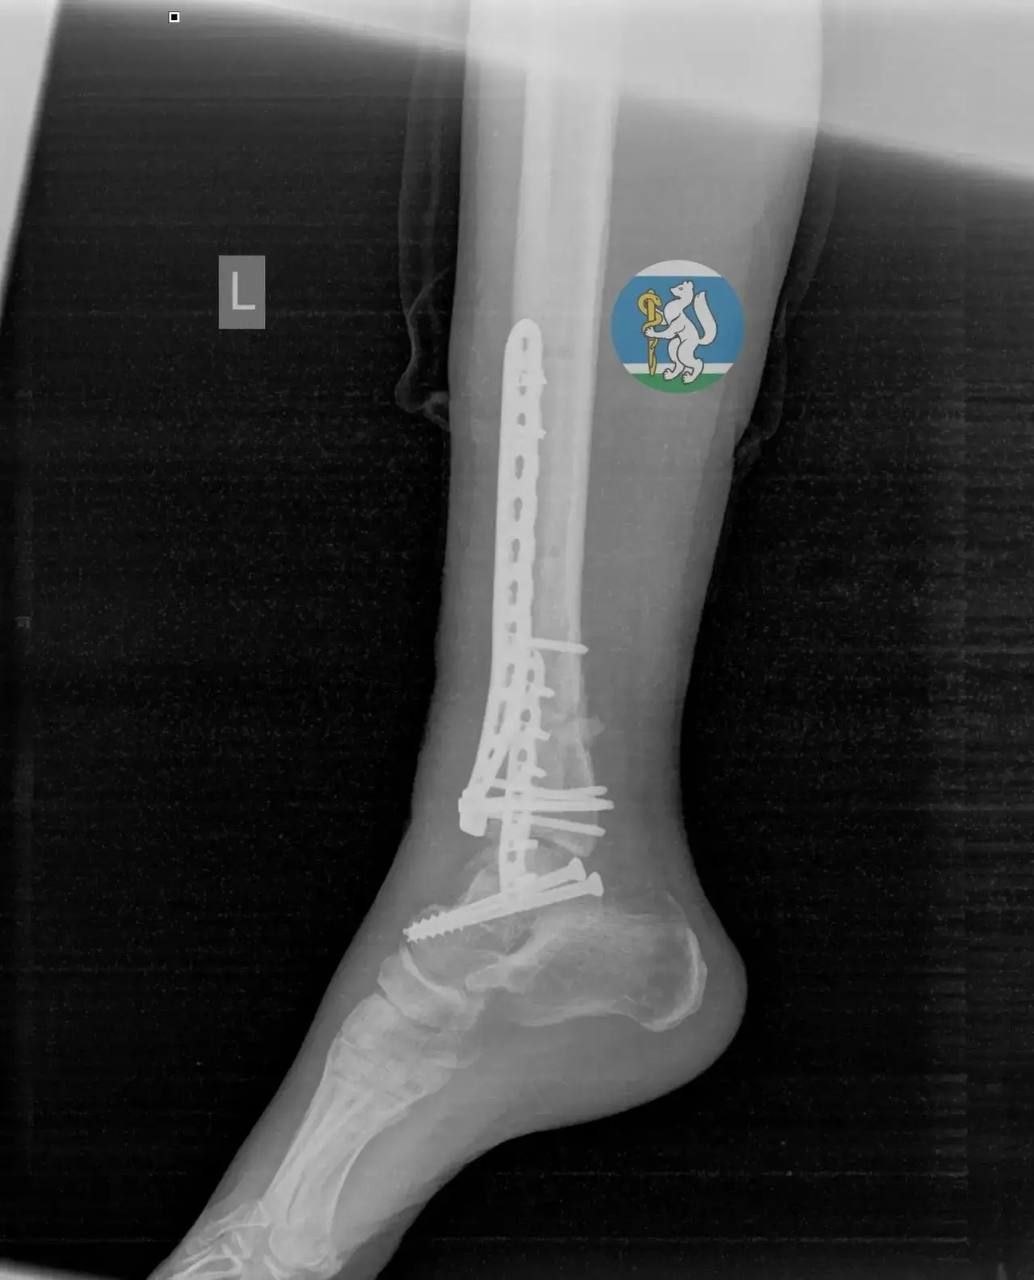

Женщина (36 лет) выпала во время мытья окна. Ее доставили в Городскую больницу №36, где диагностировали черепно-мозговую травму, повреждение позвоночника, множественные переломы таза и открытые переломы ноги – с такими травмами большинство пострадавших не доживают даже до приезда скорой.